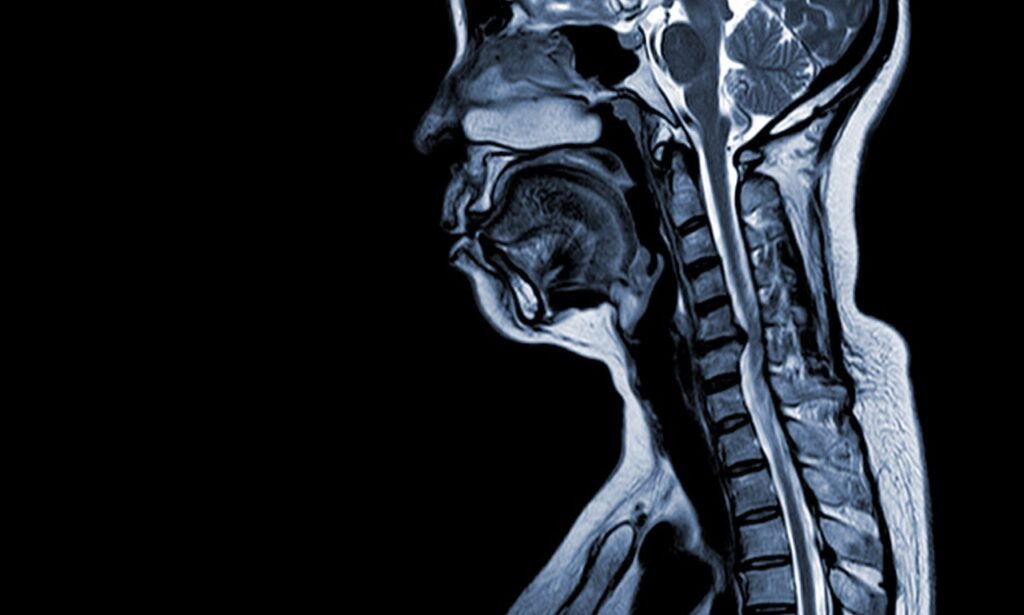

Spine MRI in Pembroke Pines: Fast Diagnosis for Back & Neck Pain

Fast Relief from Back and Neck Pain with a Spine MRI in Pembroke Pines Back and neck pain can control your entire day. You wake up stiff, struggle through work, and go to bed aching. When pain becomes a constant companion, you need answers fast. A spine MRI in Pembroke Pines provides the detailed imaging […]